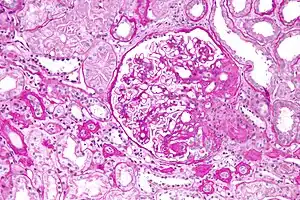

Glomeruloesclerose segmentar e focal

Glomeruloesclerose segmentar e focal (GESF ou GSF) é uma doença renal caracterizada por cicatrização (esclerose) e endurecimento de um segmento de alguns glomérulos renais. Os glomérulos são responsáveis pela filtração do sangue para remover substâncias indesejadas pela urina. Caso não seja tratado pode evoluir a insuficiência renal.

No diagnóstico, 30% dos casos já apresentam deficit de função renal. Na microscopia óptica observa-se esclerose segmentar de alguns glomérulos ou mesmo glomérulos totalmente esclerosados. A imunofluorescência mostra depósitos de IgM e C3.